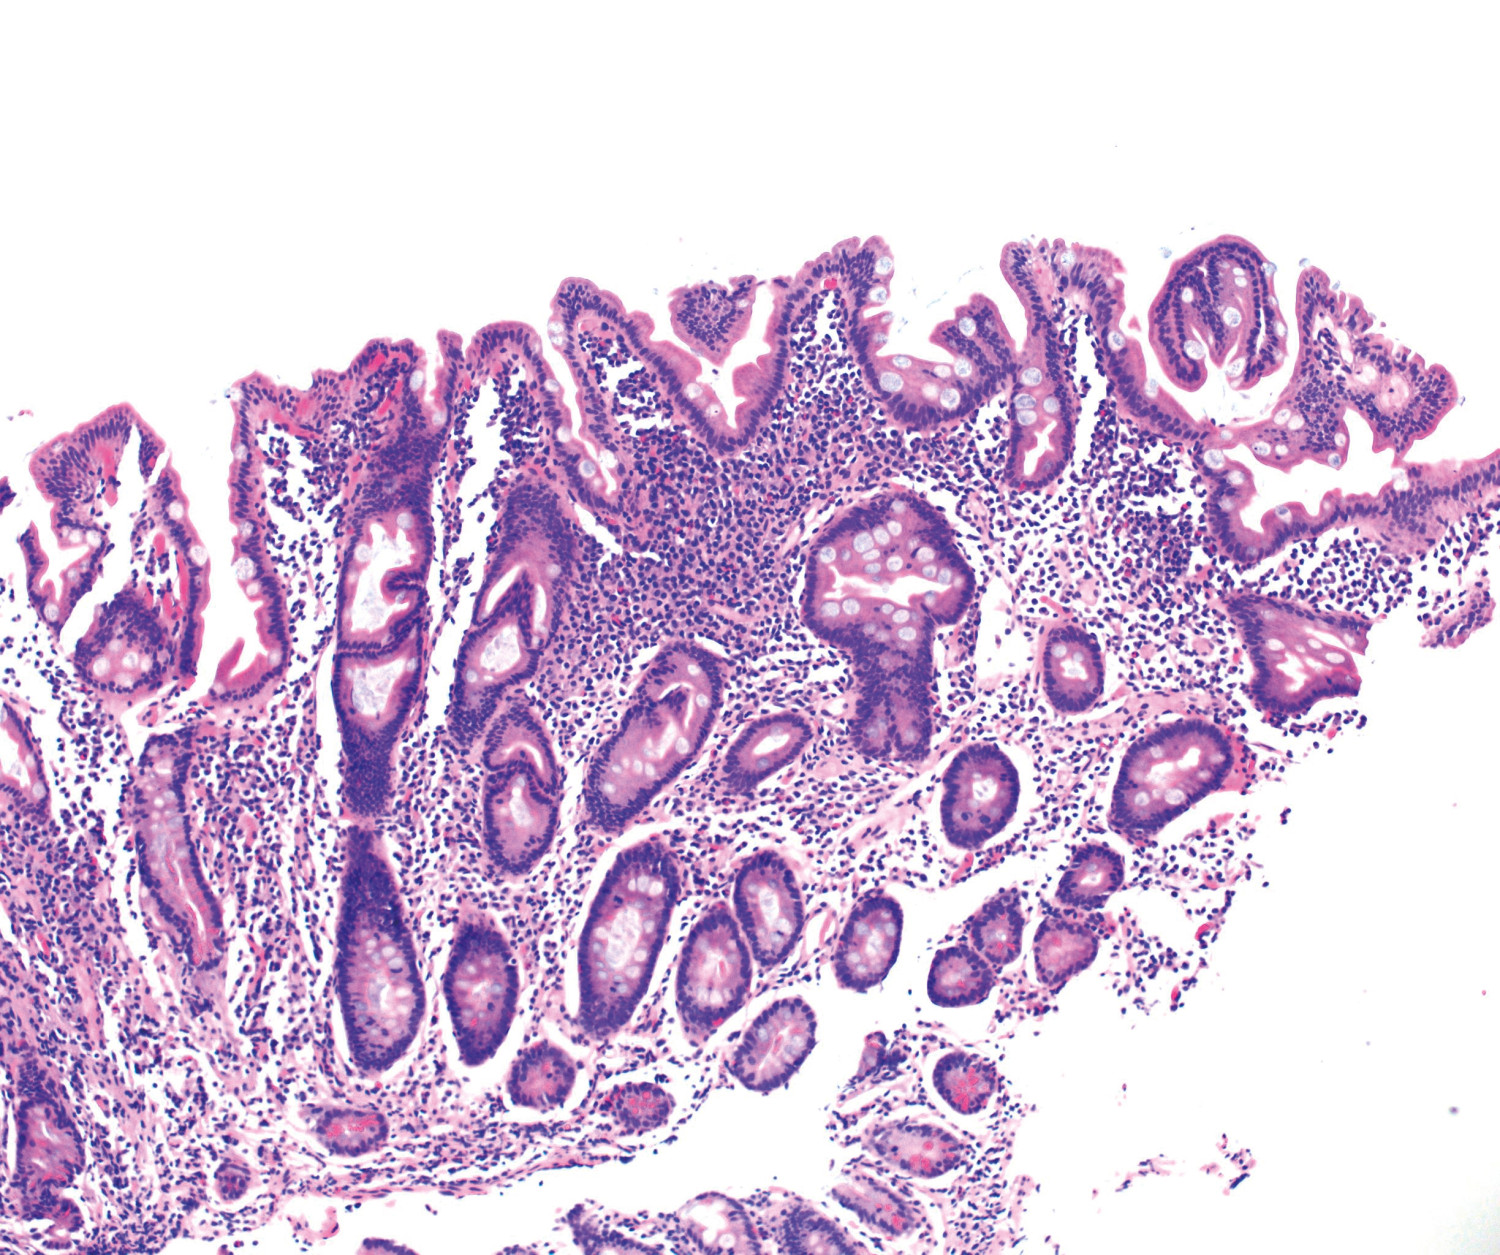

Det var ingen markant bedring etter de første dosene av vedolizumab. Gastroskopi, jejunoskopi og ileokoloskopi ble gjentatt uten signifikante makroskopiske funn. Mikroskopisk undersøkelse av alle tynntarmsegmenter viste total totteatrofi, økt mengde betennelsesceller (plasmaceller, lymfocytter og granulocytter) i lamina propria, apoptoser og fravær av begerceller i epitelet (figur 1 og 2). Det ble stilt spørsmål om autoimmun enteropati i svaret fra patologene.

Denne kasuistikken minner oss på å mistenke autoimmun enteropati hos pasienter med alvorlig malabsorpsjon, signifikant vekttap og autoimmun predisposisjon, der det histologiske bildet viser kombinasjonen av kronisk aktiv betennelse og totteatrofi i tynntarm. Cøliaki må utelukkes, enten ved negativ test for HLA-DQ2/DQ8 eller ved å vurdere behandlingsrespons på glutenfri kost. Selv ved manglende respons på glutenfri kost kan refraktær cøliaki være en mulighet, og monoklonalitet av T-celler i tarmbiopsi bør utelukkes ved flowcytometri (5) eller ved PCR-analyse for T-celle-reseptorgenrearrangering. Patologen er en viktig støttespiller, for eksempel kan mistanken vekkes ved et cøliakilignende bilde med tillegg av kronisk aktiv betennelse, apoptoser i kryptepitelet og fravær av begerceller (figur 1 og 2) (3). Positiv serumanalyse for antistoffer mot tarmepitelceller og begerceller kan styrke diagnosen, men er ikke diagnostisk (6). Andre differensialdiagnoser må utelukkes. Behandlingsresponsen er som regel god, selv ved steroidrefraktære tilstander (2).